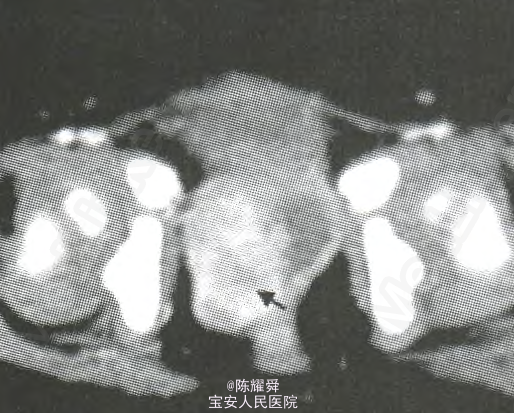

查体:会阴部流出暗红色血流,量多,腹软,无压痛、反跳痛,未及明显包块。 盆腔增强CT诊断:直肠前间隙内示不规则团块状囊实性异常强化灶.大小约3.7cm×3.2cm,直肠前间隙囊实性占位,恶性肿瘤可能大。

临床诊断:阴道卵黄囊瘤。 处理:行盆腔肿物切除术,术中探及肿瘤源于阴道经后穹窿突入盆腔,瘤体浸润整个阴道,与部分直肠前壁严重粘连。切取部分肿瘤组织送常规病检。术后病理诊断:阴道卵黄囊瘤。